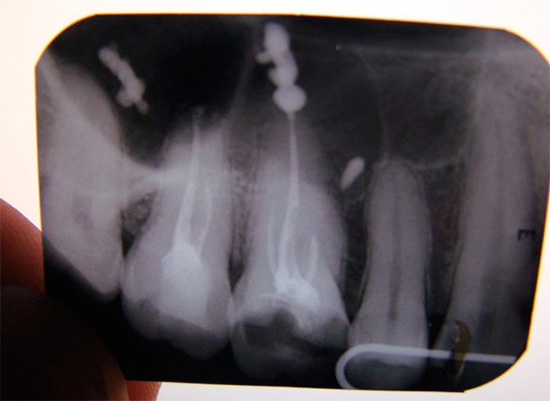

É possível diagnosticar tal complicação somente depois de estudar os dados de raios-X ou visográficos em um computador. Porém, a radiografia panorâmica de ambas as mandíbulas nem sempre permite um exame detalhado da parte superior das raízes dos dentes tratados e identifica o problema.

Se o comprimento do dente de trabalho for determinado incorretamente, não há ênfase apical, o pino de guta-percha não é dimensionado corretamente, o material é removido para a raiz do tecido circundante. Ao mesmo tempo, é possível observar no raio-x como a faixa branca do material de enchimento passa dentro da raiz, atinge seu ápice e continua. Mesmo uma pessoa que não é completamente avançada em odontologia pode diagnosticar facilmente o erro de um médico quando o alfinete de guta-percha se estende além da raiz em 4-5 milímetros ou mais.